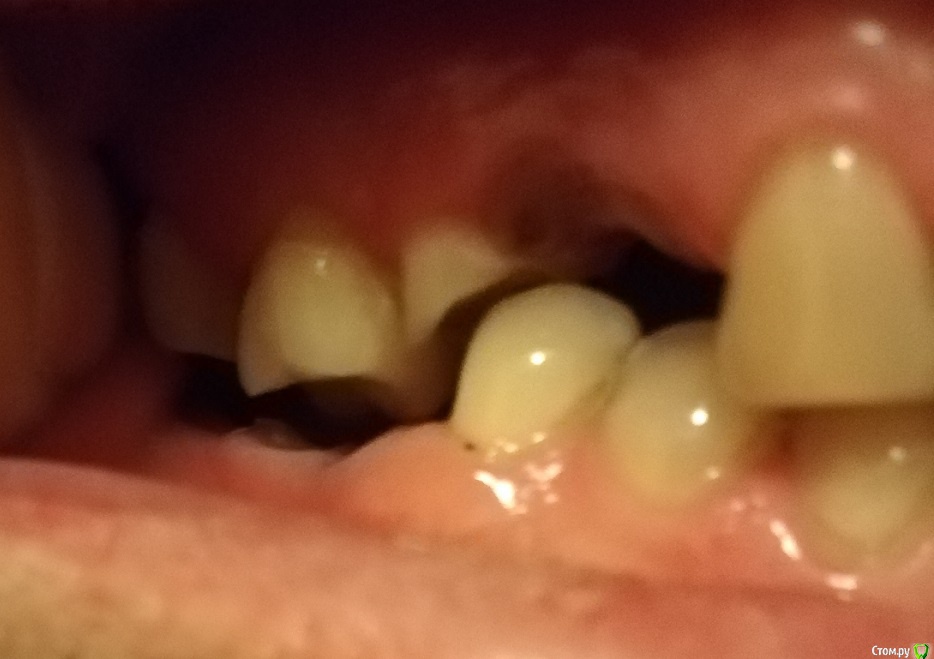

Владимир Андреевич Опубликовано 6 декабря, 2019 Автор Поделиться Опубликовано 6 декабря, 2019 Вот так это выглядит в реальности (думаю по снимку не совсем понятно) Ссылка на комментарий